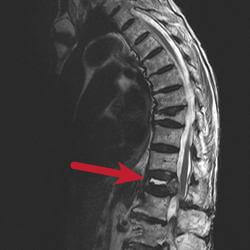

While XRays can determine whether a compression fracture exists, an MRI can determine whether it is new (acute) or chronic (old).   A compression fracture that has fluid and swelling in it is considered new and may be amenable to effective minimally invasive, interventional treatment, such as a kyphoplasty and vertebroplasty.

A compression fracture that does not have fluid is thought to be old and is usually treated conservatively with analgesics.  If the fracture is felt to be unstable, the spinal cord may be at risk of damage and surgical treatment is required.